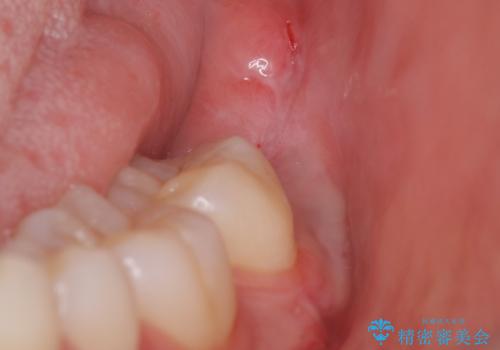

また術後丁寧に縫合をすることで治癒後の歯茎の状態もきれいにすることができます。